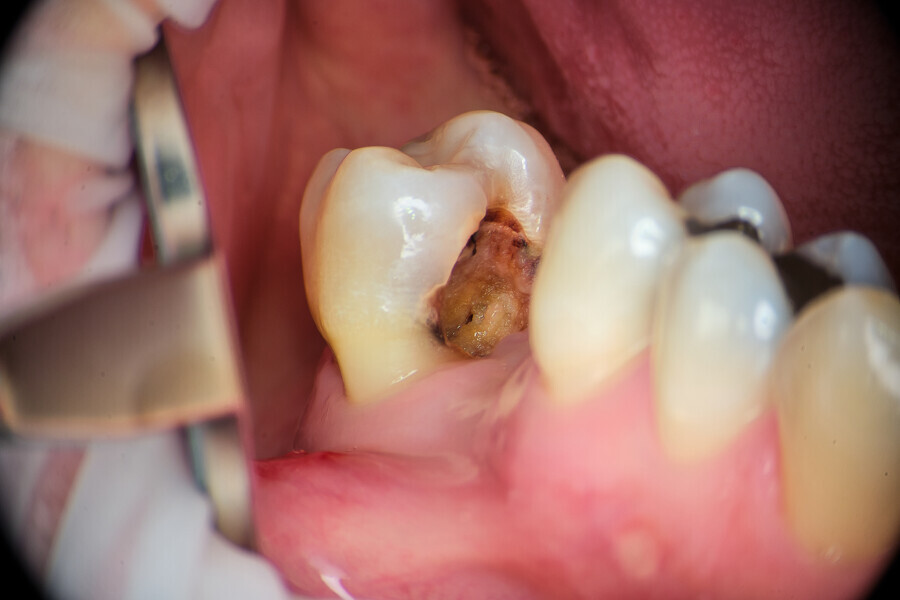

Fig.: 6

Case 1

A 43-year-old patient came to our office having been referred for endodontic treatment. During oral examination, a deep carious lesion in tooth #27 was visible. Radiographic examination confirmed the diagnosis (Fig. 6). After gingivectomy with a gingiva trimmer bur (JOTA), which was necessary in order to create space for proper isolation (Figs. 7–9), the cavity was cleaned and prepared for build-up.